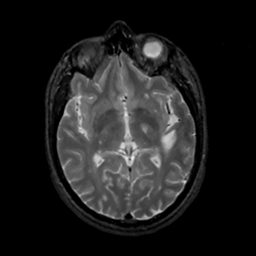

MR Study #7, March 24, 1991 -- Slice #24